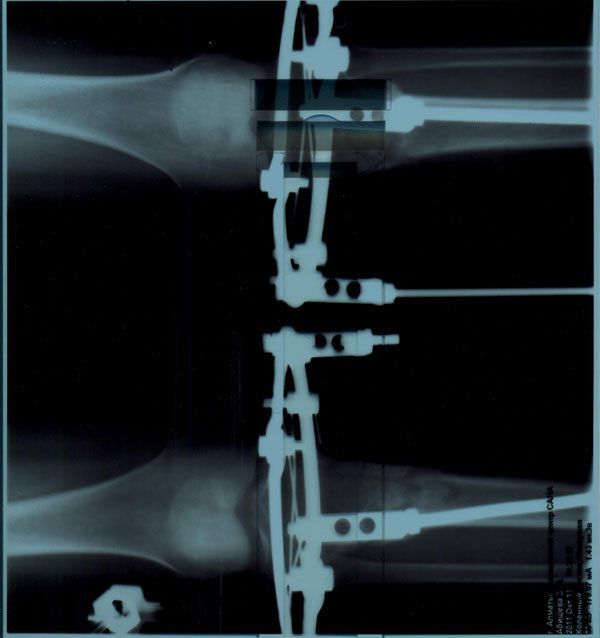

Я - Вишенка! Высылаю вам последние рентген-снимки.

посмотрите, пожалуйста.

Вишенка, приезжайте! С левой ноги 100% снятие аппаратов, на счёт правой ещё подумаем.

Здравствуйте, на рентгеновских снимках от 11.10.2011г. регенерат очень хорошей плотности. По этому можете спокойно брать билеты на конец месяца, в клинике придётся походить ещё одну недельку на распущенных аппаратах для "воспитания" костной мозоли. Поздравляю, всё идёт по плану!